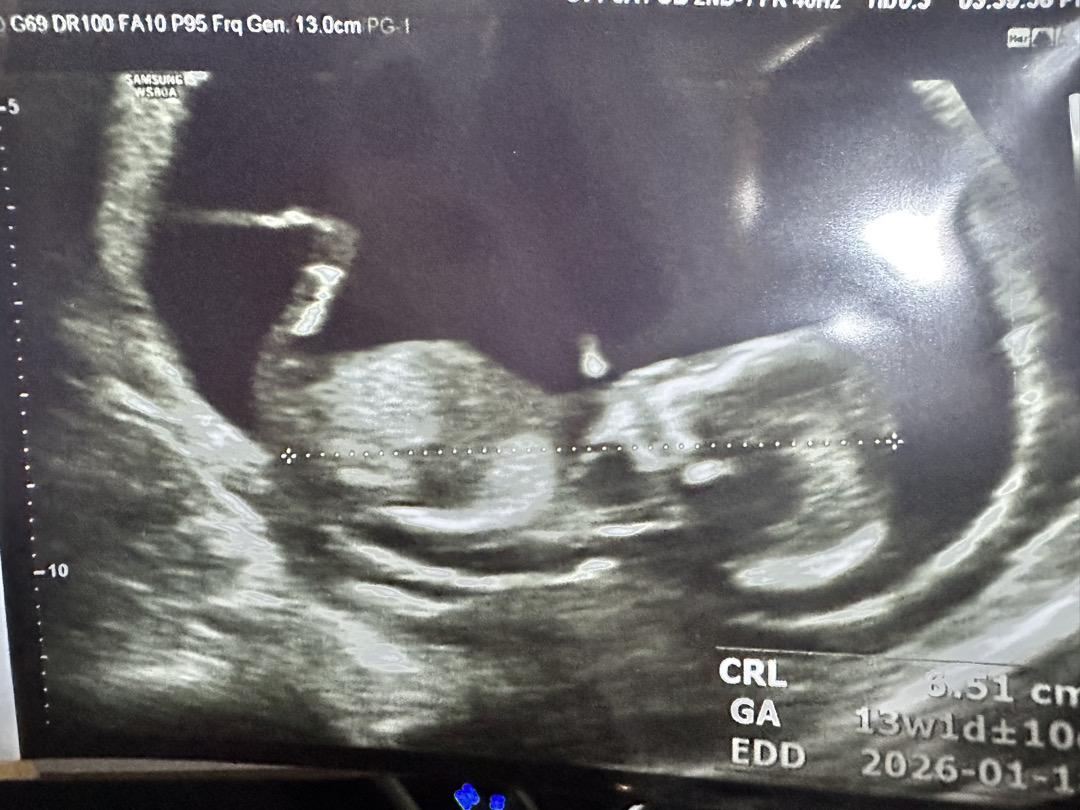

각도법 13주요

안보인다고해서 다시 한번 올려봐요